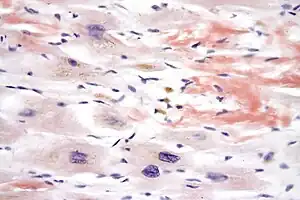

| Micrograph of cardiac amyloidosis, a cause of restrictive cardiomyopathy. Congo red stain. | |